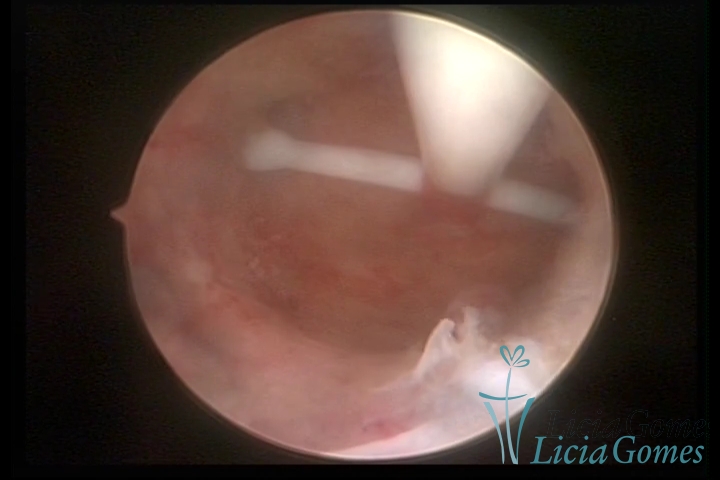

Uterine cavity with IUD

×